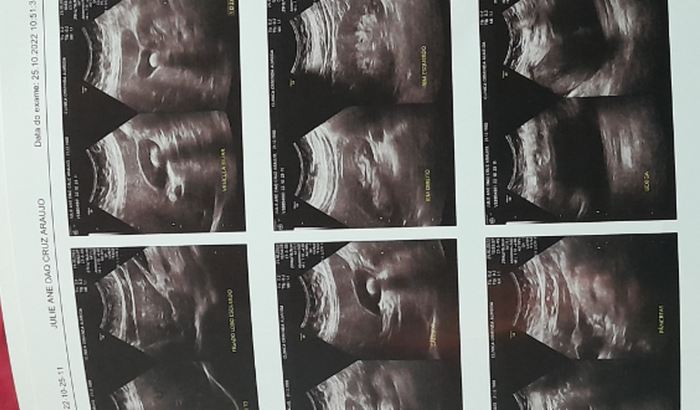

Eu sou Julie Ane, fiz essa vakinha para arrecadar 5.000,00 para fazer uma cirurgia de vesicula, pois desde outubro do ano passado tive uma crise, onde fiquei 4 dias internada sentindo muitas dores no estomago, o médico falou que precisava fazer uma ultrasson e então constou que estou com uma pedra grande na vesicula e pediu urgencia para que eu fizesse essa cirurgia. Entao ate hj espero ser chamada pelo Sus ja tem um ano e ainda estou aqui… ainda sinto dores pouca mais sinto. Estive em antas, consulta com cirurgião e ele falou que eu precisava um hospital que tivesse mais recurso. Entao estou aqui nas maos de Deus. Peço encarecidamente a todos que puderem me ajudar com qualquer quantia. Pra que eu possa ta fazendo essa cirurgia. Tenho medo de dá outras crises quem ja teve sabe o quantoé ruim o quanto dóii. Minha cidade não tem recurso nenhum. Pelo amor de Deus me ajudem!!!! Obrigada a todos que puderem me ajudar.